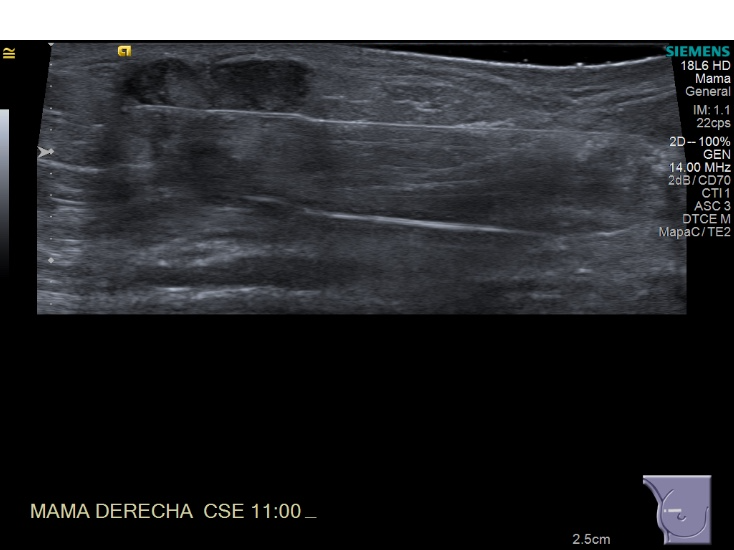

Crioablacion de tumor en mama derecha